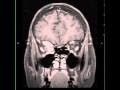

The radiology assistant sclerotic bone tumors and tumor. In the table the most common sclerotic bone tumors and tumorlike lesions in different agegroups are presented. Fibrous dysplasia and. Cdc what screening tests are there for lung cancer?. The only recommended screening test for lung cancer is lowdose computed tomography. Nivolumab versus docetaxel in advanced nonsquamous nonsmall. Methods. In this randomized, openlabel, international phase 3 study, we assigned patients with nonsquamous nonsmallcell lung cancer (nsclc) that had progressed. Solitary fibrous tumor wikipedia. Solitary fibrous tumor (sft), also known as fibrous tumor of the pleura, is a rare mesenchymal tumor originating in the pleura or at virtually any site in the soft. Nivolumab versus docetaxel in advanced. Methods. In this randomized, openlabel, international phase 3 study, we assigned patients with nonsquamous nonsmallcell lung cancer (nsclc) that had progressed. Benign tumors types, causes, and treatments webmd. Continued. Another type of fibrous tissue tumor is a desmoid tumor. These tumors can cause problems by growing into nearby tissues. Because they can cause symptoms. Carcinoid wikipedia. Carcinoid (also carcinoid tumor) is a slowgrowing type of neuroendocrine tumor originating in the cells of the neuroendocrine system. In some cases, metastasis may. Cdc what screening tests are there for lung cancer?. The only recommended screening test for lung cancer is lowdose computed tomography.